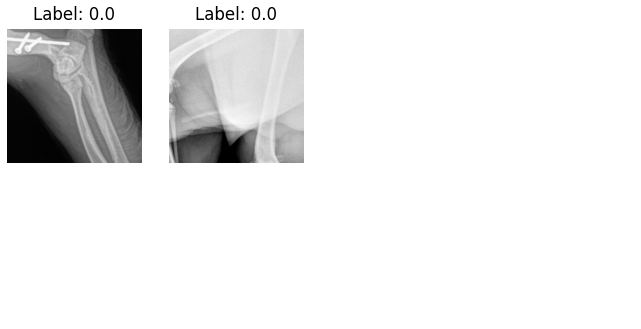

The study utilizes a dataset comprising 3970 veterinary radiology images associated with limb fractures (80/20 train test split). The identification of aberrant predictions is facilitated through the analysis of regions within the images that significantly influence the classifier’s predictions. To further elucidate the framework’s capability in identifying aberrant predictions, two complementary evaluation methods were employed.

Saliency-map-crop evaluation The saliency maps were initially evaluated using fracture mask bounding box labels provided by expert veterinarians. The metric we employ, which we refer to as Saliency Crop Accuracy (SCA) is a specialized adaptation of the Intersection over Union (IoU) metric commonly used for object detection tasks [52]. Unlike traditional IoU focusing solely on overlapping areas between predicted and ground-truth bounding boxes, SCA considers the centroids’ distance when no overlap occurs, introducing a decay factor proportional to the inverse of this distance. A high SCA value indicates a likely accurate prediction, while a zero value signifies misdirection in the saliency map. This evaluation suggests that all aberrant predictions will exhibit a very low saliency map accuracy metric value, which serves as a quantifiable measure of the aberrance of the predictions.

Visual inspection However, the saliency map metric alone may not capture the complete picture, especially in scenarios where reasonable-looking regions did not contain a fracture (i.e. the SCA will be low, but the prediction is not aberrant). To address this limitation, a visual inspection of the predictions in each scenario was carried out. This dual-method evaluation motivates a more holistic approach to understanding ‘accuracy’, emphasizing the importance of not only examining the alignment between the saliency maps and ground truth but also scrutinizing the logical coherence of the identified regions.